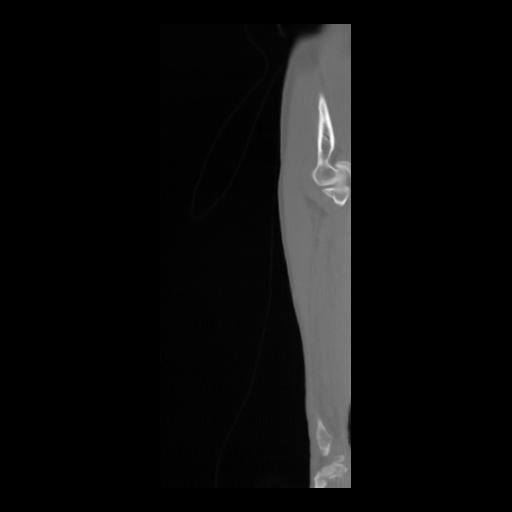

36 CUERPO,CE,Sagittal,3.000,CUERPO,Sagittal,